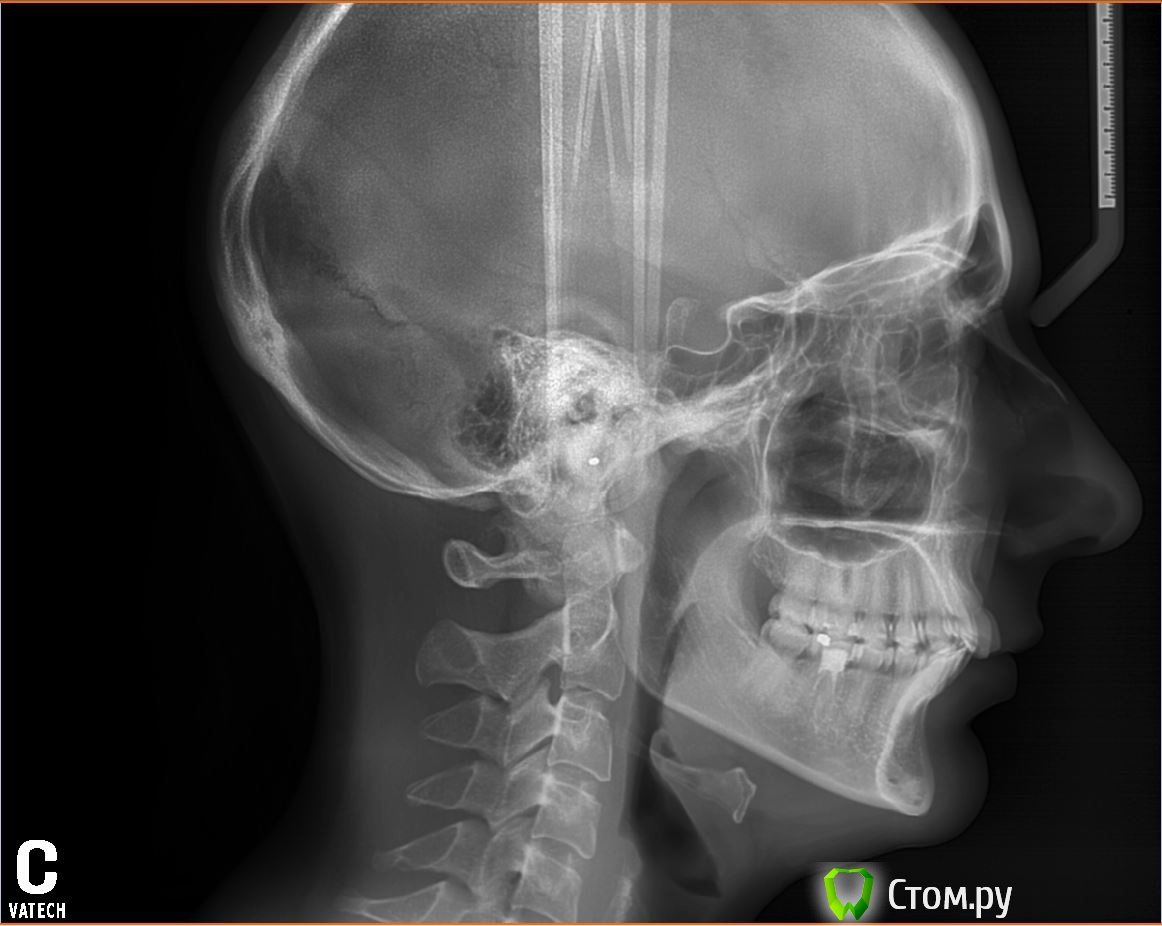

arTika Опубликовано 2 июля, 2014 Поделиться Опубликовано 2 июля, 2014 Здравствуйте, уважаемые доктора!!!Уже несколько лет щелкает сустав при открывании рта, челюсть двигается вниз с-образно. К этой проблеме добавился шум в ушах, иногда боли в области виска, бывает так, что открывая рот не могу завершить движение, как бы заклинивает челюсть. Зубы раньше стояли ровно, постепенно стали наклонятся в разные стороны. Щелчки в суставах стали беспокоить уже после, появления скученности. Хочу начать лечение, была на консультации у ортодонта. Врач сказал, что зубы выровнять мне может, но сустав во время лечения может еще сильнее болеть, в итоге ортодонт обещает, что результатом будут только ровные зубы, с внчс ситуация не изменится. Но я не с эстетической стороны хочу начать лечения, меня больше беспокоит ситуация с суставом, так как очень быстро ситуация ухудшается. Была на консультации у ортопеда, мне рекомендовали удалить все 8-рки, сделали слепки. 8-рки мне удалили. Сейчас ортопед назначил трг и дальше брекет лечение( при этом возможно необходимо удалить все 4 на н/ч и на в/ч) у ортодонта, а после брекетов уже приходить к ортопеду. Снимок сустава никто не назначал. На форуме читаю, что тем у кого проблемы с суставом сначала изготавливают капы и если нужно потом брекеты. Поэтому я переживаю, что если сейчас мне просто приклеят брекеты, зубы станут ровными, а суставам станет только хуже и я вообще не смогу открывать рот или мне прийдется искать у кого перелечиваться, а это еще сложнее, ведь врачи этого ох, как не любят. Скученность сильная, но раньше зубы стояли ровно до появления 8-рок, значит им места хватало, тогда зачем сейчас удалять здоровые 4-рки?В связи с этим у меня возникли вопросы:1. С чего начинать лечение? С брекетов или индивидуальной капы?2. Если с капы, то какая нужна?3. Нужно ли удалять 4-рки? Если удалять, то как это повлияет на внешность в моем случае, ведь челюсть и так узкая?4. Нужно ли до лечения делать снимки самого сустава? Если да, то какие?5. Можно ли вообще добиться выздоровления сустава в моем случае?Я понимаю, что заочно сложно давать консультацию, но врачи в нашем городе такое впечатление, что сторонятся пациентов с нарушениями внчс, меня отсылают от одного врача к другому, как будто никто не хочет брать на себя ответственность (или не может) и лечение не начинается, Помогите мне пожалуйста!!!! Порекомендуйте врача, который сможет помочь и вылечить меня!Если нужно могу выложить фото слепков, которые мне сделали. Заранее спасибо всем! Ссылка на комментарий